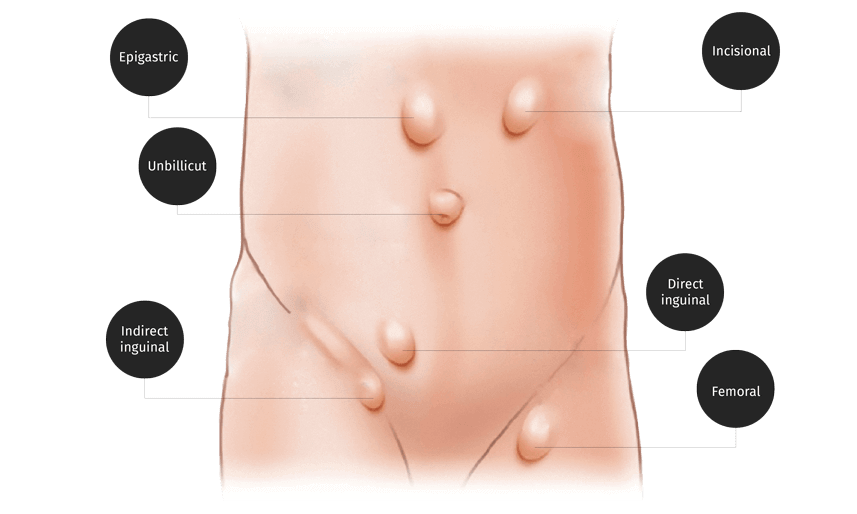

About Hernia

Hernia is a very common disorder and affects about 3% of the population; hence it is important for all to have basic knowledge of this problem, its symptoms and treatment.

It can occur in males as well as females but it is more common in males. Hernia can occur at any age, from cradle to grave; it may be seen in a newborn child as also in a very old person. Every Hernia needs immediate detection by medical expert, proper and detailed diagnosis followed by proper treatment.